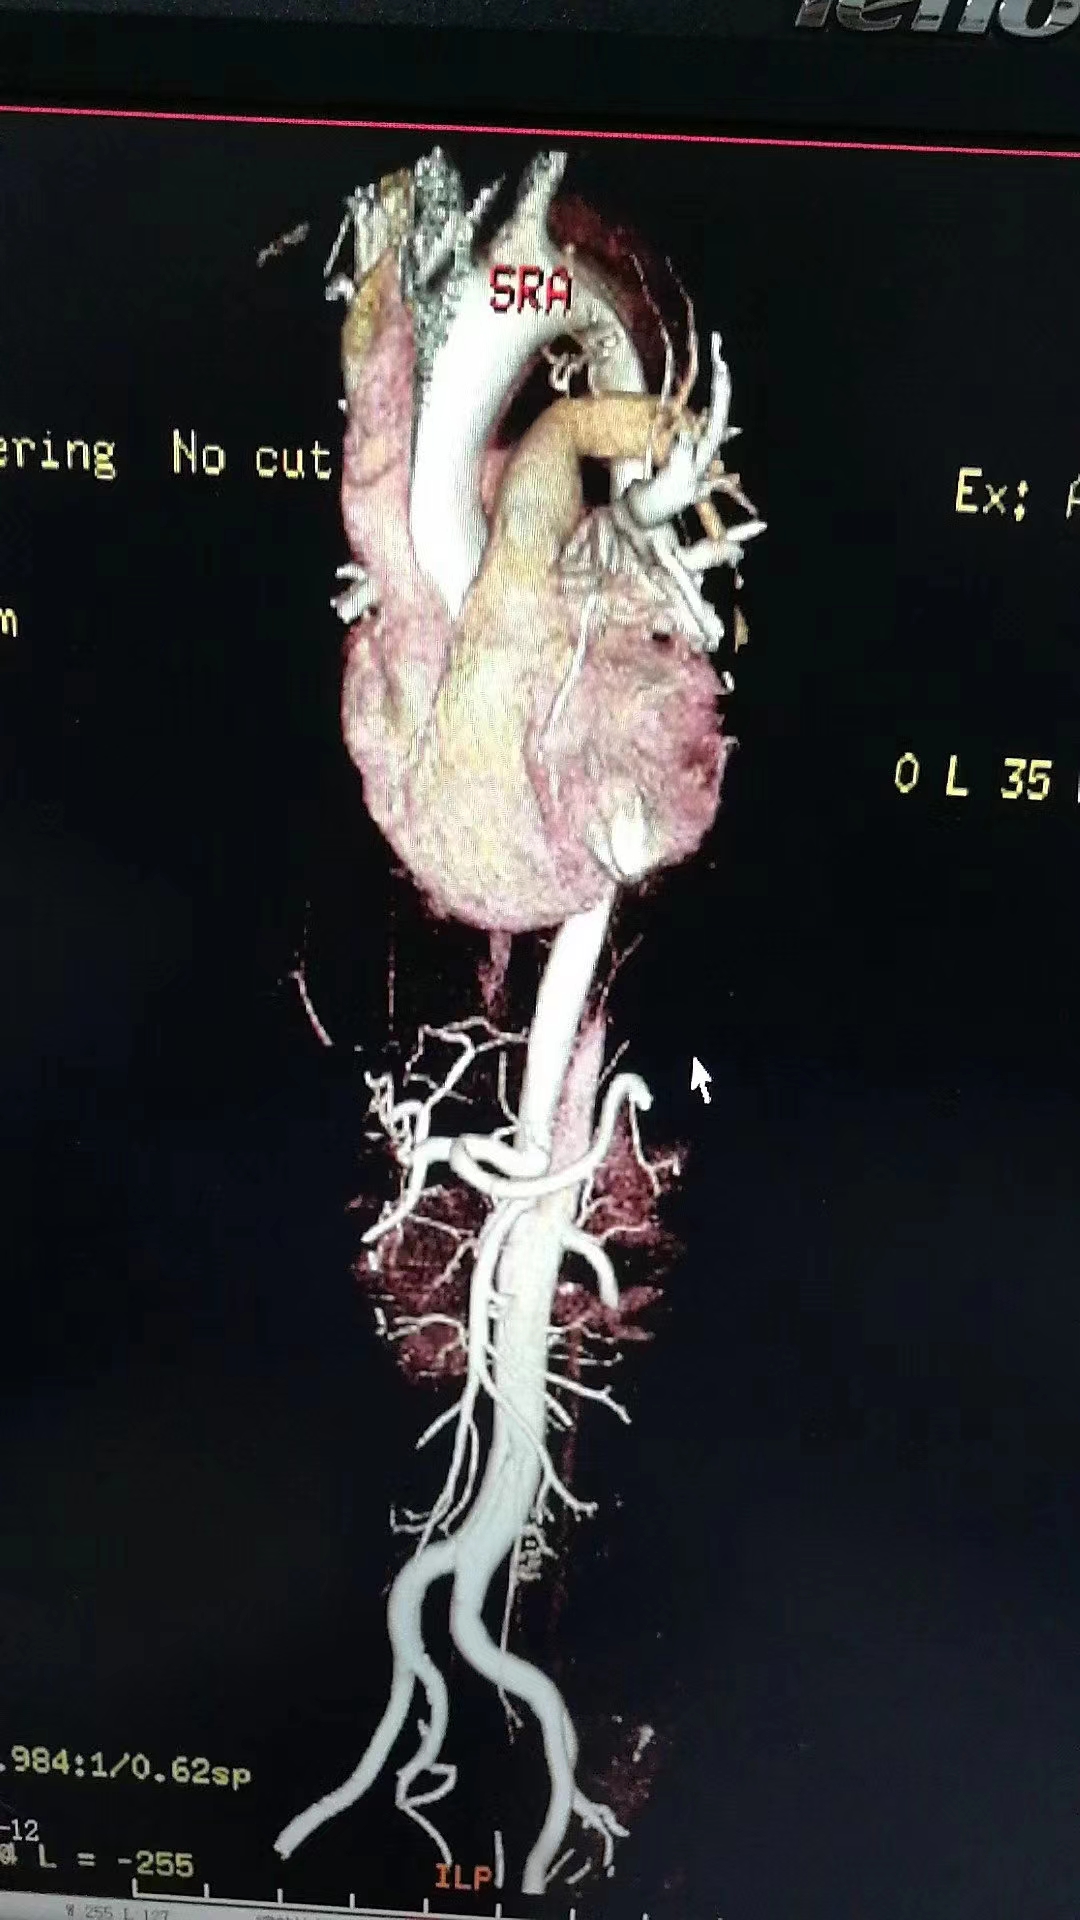

反复询问患者后一个细节引起了我的注意,患者描述她最开始只是颈部疼痛,不知道怎么回事疼痛一下就窜到腰部去了,这让我联想到了主动脉夹层。于是我立即与患者及家属沟通后完善了主动脉CTA,主动脉CTA提示主动脉夹层I型。后来这个病人转院做了主动脉置换手术,手术很顺利,术后患者也恢复得很好。

影像学检查目的是要对全主动脉进行综合评价,包括受累的范围、形态、不同部位主动脉的直径、主动脉瓣及各分支受累情况、与周围组织的关系,以及其他相关表现如心包积液、胸腔积液及脏器缺血情况等。